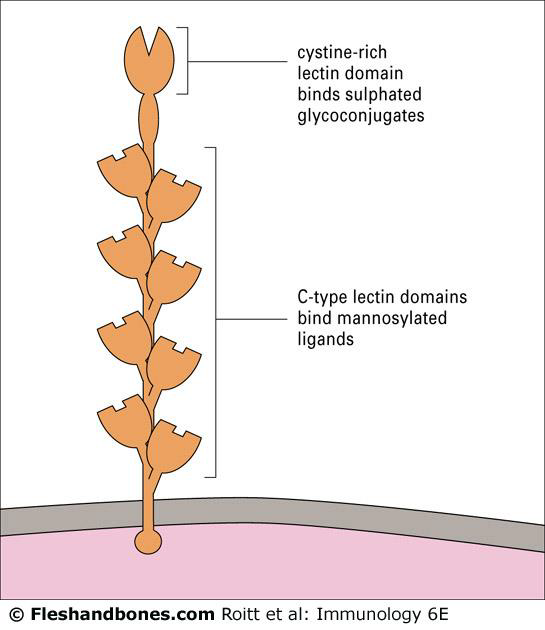

C 型凝集素(C-type lectin-like family)

- 辨認抗原

- Mannose receptor

Lectin

- Mannose-binding lectin(MBL) 直接認糖類抗原

- 產生 C4b2a